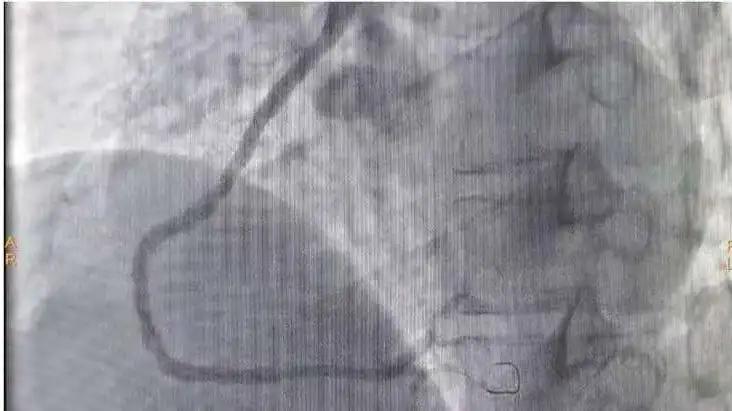

手术后